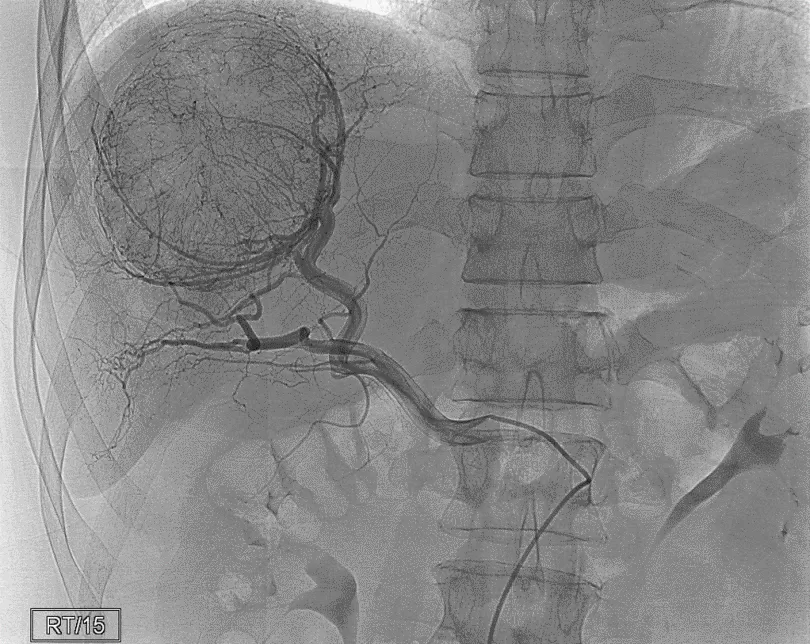

Các bệnh lý có thể hưởng lợi từ công nghệ xạ trị hiện đại trên hệ thống máy gia tốc Elekta Infinity

Xạ trị là phương pháp điều trị sử dụng các tia bức xạ năng lượng cao nhằm tiêu diệt tế bào ung thư. Theo số liệu của Cơ quan Năng lượng Nguyên tử Quốc tế ...